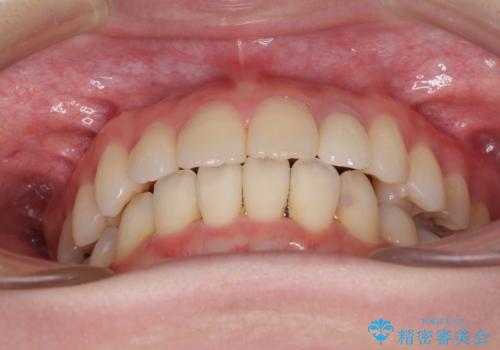

抜歯矯正は2年から2年半程度の治療期間を要することが一般的ですが、僅か1年1ヶ月で終了しました。

あっという間に気になっていた歯並びが改善し、患者様には大変満足していただきました。